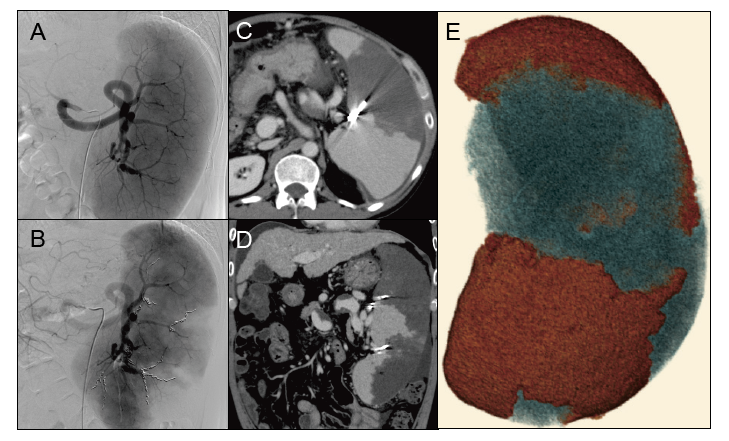

Partial splenic embolization (PSE) in Case 1.

A:Severe splenomegaly was detected on selective splenic arteriography.

B:Microcoils were placed (two metallic coils in the superior branch 2, one in the mid branch 1, three in the mid branch 2, and three in the inferior branch.

C, D:Computed tomography (CT) on day +9 showed less intense enhancement of the embolized area than the non-embolized area. Small amounts of ascites were observed around the liver and spleen.

E:Three-dimensional image of the spleen. The red and blue areas indicate non-embolized (1,150.0 cc) and embolized (600.32 cc) areas, respectively. Post-PSE CT imaging revealed the embolization rate to be 34.3%.